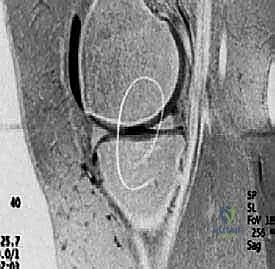

2. Magnetic Resonance Imaging (MRI): Our gold standard for cartilage assessment. MRI clearly demonstrates lesion size, location, depth, involvement of subchondral bone, and the number of lesions. Advanced sequences like T2-weighted mapping provide remarkable detail at the proteoglycan level, helping us assess cartilage quality and integrity. Postoperatively, MRI is invaluable for assessing defect fill, integration, and subchondral bone status.

FIG 3 • C. MRI of articular cartilage lesion ( circled ) of the medial femoral condyle.